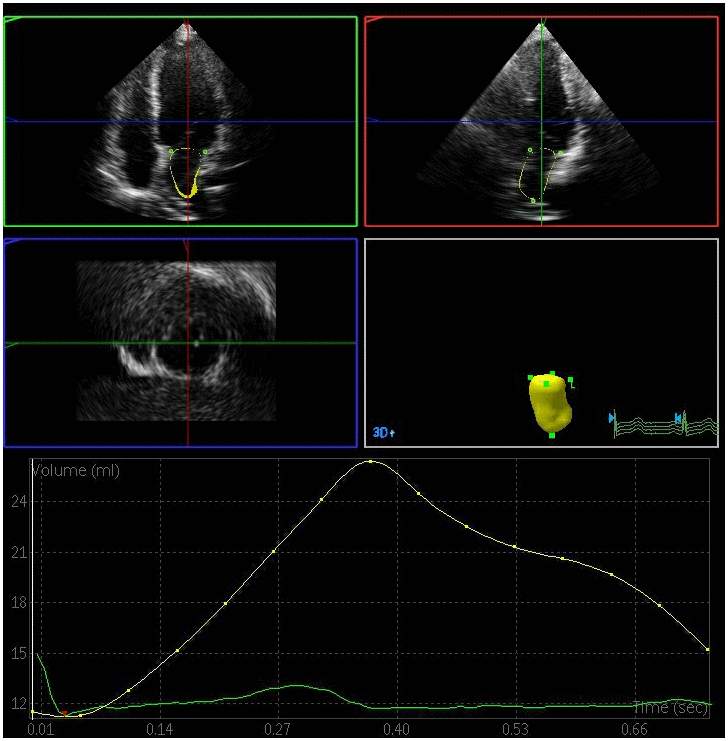

The left atrial maximum volume (LAVmax), left atrial pre-systolic volume (LAVp), and left atrial minimum volume (LAVmin) were significantly elevated in the DN and DM groups relative to the control group, whereas the total left atrial ejection fraction (LAEFt) and passive left atrial ejection fraction (LAEFp) were significantly lower in the DM and DN groups relative to the control group (P < 0.05) (Figures 1–3). The left atrial maximum volume index (LAVImax), left atrial pre-systolic volume index (LAVIp), and left atrial minimum volume index (LAVImin) were also significantly elevated in the DN group relative to the DM group, whereas the LAEFt and LAEFp parameters were significantly lower in the DN group relative to the DM group (P < 0.05). We also found that active left atrial ejection fraction (LAEFa) was significantly higher in the DN group relative to the DM and control groups (P < 0.05), whereas this parameter did not differ significantly between the DM and control groups (P > 0.05) (Table 3).

Figure 1. Left atrial volume quantification by RT-3DE of a case in control group.